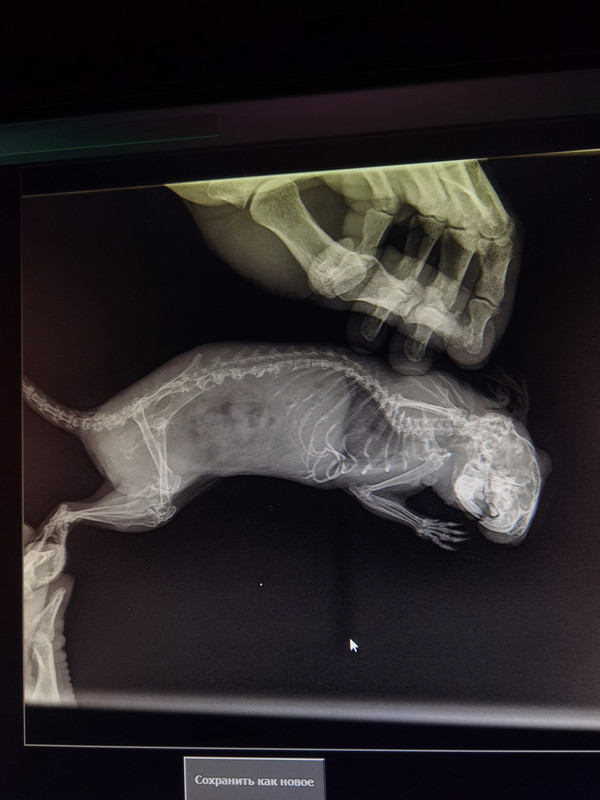

Он не чувствует полностью сами ступни, приложу снимки рентгена, в ветклинике сказали, что кости в задних лапах очень слабые. Он пытается двигать самой лапой в принципе, но ступни не чувствует, реакции никакой на них нет. Лапы вроде пока не грызёт, но вот хвост продолжает грызть. В ветеринарной выписали ветмедин, потому что нашли проблемы с сердцем, мелоксидил для обезбаливания, ничего точного не сказали, назначали повторный приём на субботуElena N.N писал(а): ↑03 мар 2022, 05:06 добрый день, не увидела раньше Ваше сообщение. Трудно сказать почему так быстро развилось такое состояние. Это параплегия или паралич? Параплегия — это снижение мышечной силы с ограничением объема произвольных движений. Паралич — это полная неспособность к выполнению движений. Различие в процессах происходит из за разной причины и как следствие - разное лечение. Лапки совсем не двигаются? Холодные? дегу их грызёт? при подергивании и пощипывании за лапки что-то чувствует?

я вижу немного другое. Вот дегу Юли, это нормальные косточки и снимок Вашего дегу, обратите внимание на косточки задних лап, те, которые на Вашем снимке выделены кружочками

на снимках Вашего дегу идёт распад надкостницы и перерождение структур коленных суставов. Мелоксикам, да, видимо пожизненно, проблем с сердцем на таком снимке не видно. В Вашем случае я бы ещё добавила витамин Д по 1 капле 2 раза в неделю и хондроитин или аналоги, типа ГХК, 1\6 или 1\8 таблетки, но не факт что поможет....

давайте ближе посмотрите, что с косточками произошло

он не слабые, они перерождаются, по типу "остеопороза", также известный как потеря костной массы, который является метаболическим заболеванием скелета, при нём кости теряют свою нормальную структуру. Они становятся пористыми и хрупкими. Заболевание протекает на первых порах бессимптомно.

возможно по типу накопительного эффекта-было плохо, но не так, потом начались проблемы с иннервацией и ещё посмотрите на структуру позвонков в хвостике, там тоже полная деструкция , то же самое может быть и с позвонками в поясницы, а это будет ущемлять нервные окончания задних лапок и хвоста